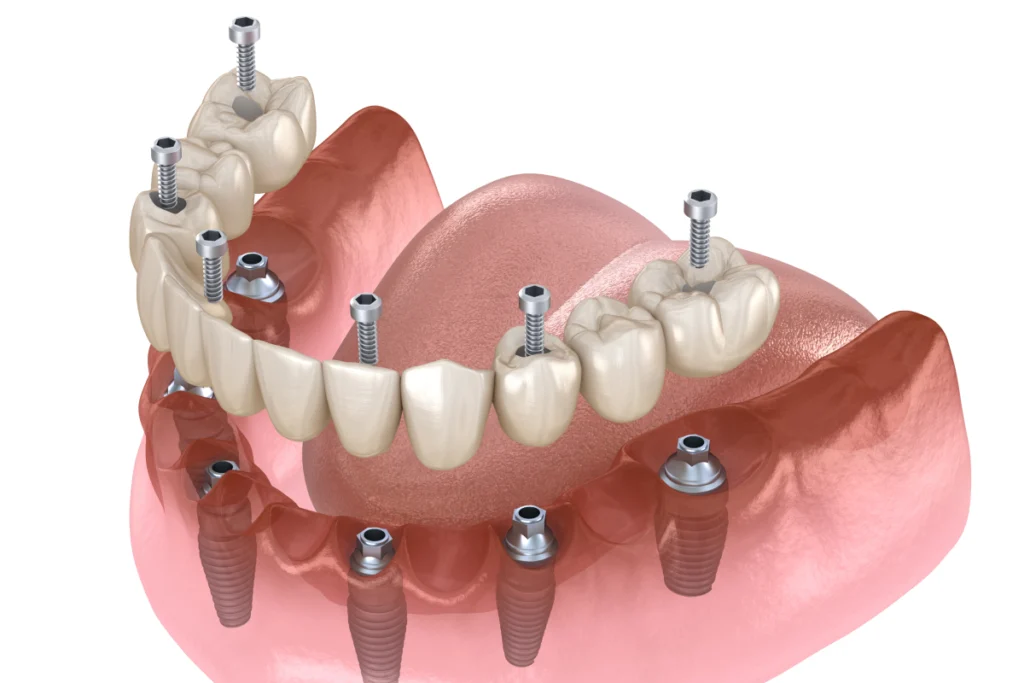

La greffe osseuse est souvent nécessaire avant la pose d’un implant dentaire, en particulier chez les patients ayant subi une perte osseuse importante. Elle consiste à prélever de l’os au niveau du menton, de la mâchoire ou d’une zone donneuse pour l’intégrer au site receveur. Le dentiste peut également utiliser des matériaux synthétiques ou des biomatériaux pour augmenter le volume osseux.

Cette intervention permet de recréer une base solide pour l’implant et améliore la stabilité de la future prothèse. Après la greffe, une période de cicatrisation de plusieurs mois est généralement nécessaire pour permettre l’intégration de l’os.

Chirurgie pré-implantaire

La chirurgie pré-implantaire prépare la mâchoire à recevoir des implants dentaires en corrigeant les défauts osseux ou les irrégularités gingivales. Le dentiste peut réaliser un comblement de sinus (sinus lift) pour augmenter la hauteur osseuse dans la région postérieure de la mâchoire supérieure. Il peut également effectuer une régénération osseuse pour renforcer la zone de pose de l’implant. En outre, il peut remodeler les tissus mous pour garantir une meilleure esthétique autour des implants. Ces interventions augmentent la stabilité de l’implant et assurent un résultat fonctionnel et esthétique durable.

Techniques courantes :

- Élévation du sinus (sinus lift) pour augmenter la hauteur osseuse dans la mâchoire supérieure

- Expansion de la crête osseuse pour élargir la zone de pose de l’implant

- Greffes de tissus conjonctifs pour renforcer les gencives

Les implants dentaires sont-ils possibles après une extraction ?

Oui, nous pouvons poser un implant dentaire après une extraction. Dans certains cas, nous réalisons toutefois une greffe osseuse afin de garantir une base suffisamment solide pour accueillir l’implant.